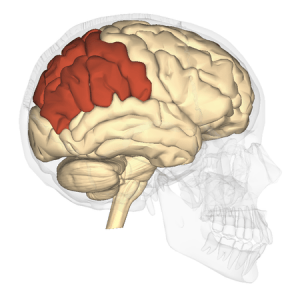

El lóbulo frontal es uno de los 4 lóbulos del hemisferio cerebral.

Este lóbulo controla varias funciones como la resolución de problemas, pensamiento creativo, juicio, intelecto, atención, comportamiento, reacciones físicas, pensamiento abstracto, movimientos coordinados, músculos coordinados y personalidad.